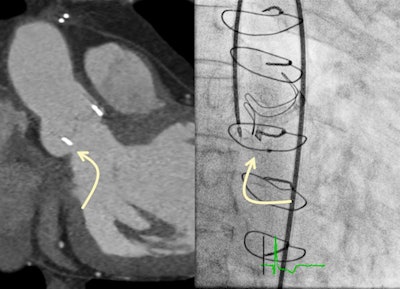

Achenbach is chairman of cardiology and a professor of medicine at the University of Erlangen, Germany, and he became ESC president in September 2020. He won the 2017 Minnie award for Most Influential Radiology Researcher. His research interests focus on cardiovascular imaging, mainly CT, for the early detection and characterization of coronary atherosclerosis, and for the support of coronary and cardiovascular interventional procedures.

A: As before, we are working on the relationship between cardiac imaging and cardiac intervention. This is what excites me most at this point in time.

Imaging is superbly important to permit and to move ahead all the new structural heart interventions.